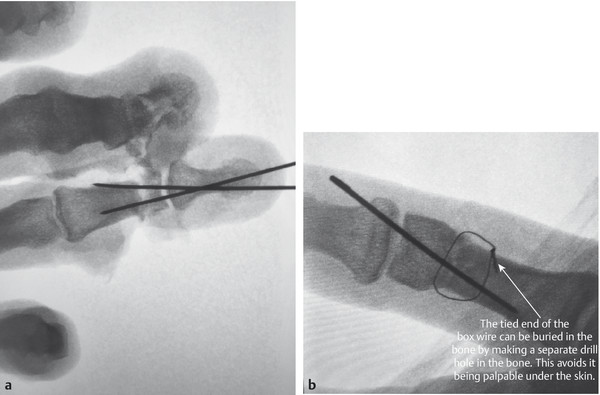

Fig. 12.17 (a,b) Alternative methods of osteosynthesis include retrograde cross K-wire fixation or a single K-wire and a loop of interosseous wire described by Lister.

Fig. 12.18 Completed intraoperative 90–90 box wiring.